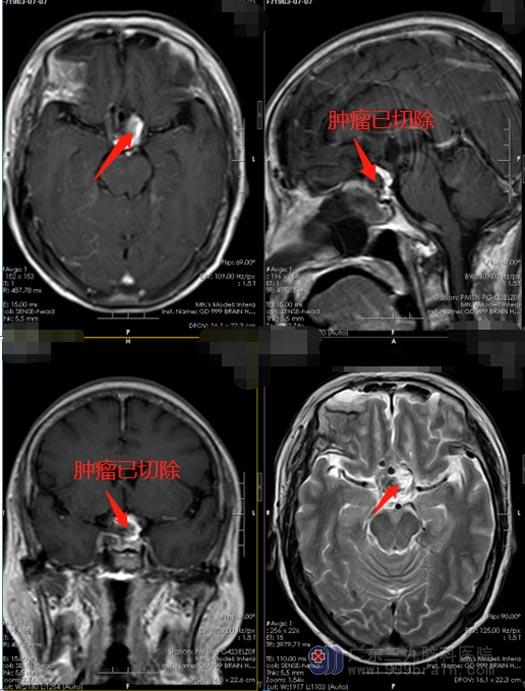

鞍结节脑膜瘤的一线治疗是完全切除肿瘤,使患者视力正常化,避免手术并发症。在过去的十年中,这些结果是通过使用开颅手术来实现的。最近,通过鼻窦腔的前侧入路越来越多地运用于手术,也可以达到同样的目的。与开颅手术相比,经鼻内镜手术对于鞍隔部分硬脑膜的处理更彻底,术中不牵拉视神经,对穿通支的保护也优于开颅,绝大多数鞍结节脑膜瘤不涉及到垂体柄和下丘脑,被认为是一种相对于开颅术更小创伤的替代方法。

了解这些以后,特别是看到同病房经鼻子手术过的病友恢复得都挺快,吴阿姨一家人轻松了许多。1月21日,鲁明带领团队为患者行“内镜扩大经鼻蝶鞍结节脑膜瘤切除术”,术后当天,吴阿姨就清醒,第二天就惊喜地发现左眼视力恢复了很多,可以看清楚眼前的东西。重获了光明,没有出现那些胆战心惊的并发症,最开心的除了吴阿姨,还有她的女儿。